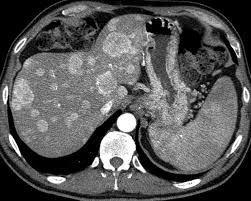

• Əksər hallarda (70%) çoxsaylı olur və qaraciyərin hər iki payını tutarlar.

• Ölçüləri bir neçə millimetrdən bir neçə santimetrə qədər dəyişə bilər.

• Əksəriyyəti arerial qanla qidalanırlar, sürətli qan axınına malikdirlər, lakin hipovaskulyardırlar.

• Törəmə ətrafında kapsula olmur, lakin reaktiv bölgə ola bilir ki, bu da USM-də hipoexoik haşiyə kimi görünə bilir.

• Görüntüləmədə bədxassəli şişlərə məxsus kontrastlaşma (arterial fazada periferik kontrastlaşma, venoz fazada yuyulma).